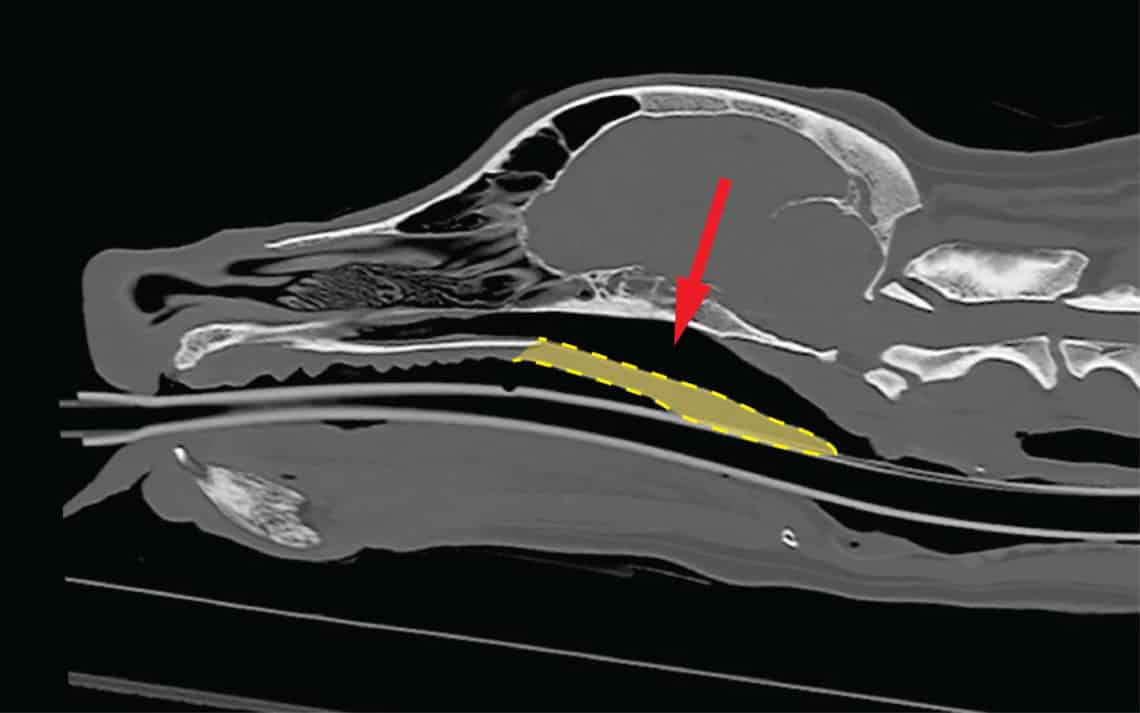

In a healthy dog, the soft palate is the tissue at the back of the roof of the mouth that ends cleanly, allowing air to flow freely into the windpipe (trachea).

• In a Normal-Snout Dog (Dolichocephalic): The soft palate is the correct length and ends well above the opening to the larynx (voice box), as seen on an X-ray. There is a clear, open passage for air.

• In a Flat-Faced Dog (Brachycephalic): The soft palate is too long for the short skull. On an X-ray, you can see the excess tissue extending far down into the back of the throat, partially blocking the laryngeal opening. This obstruction is the source of all that noisy, labored breathing.